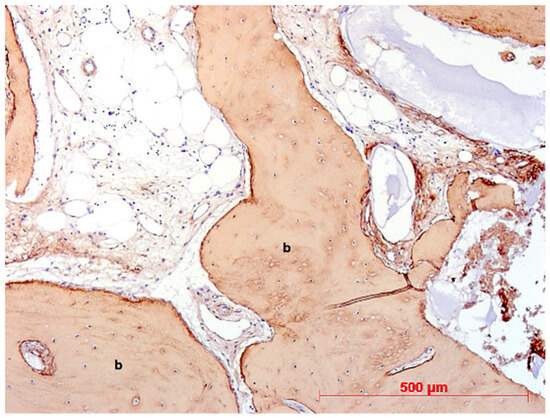

2.2. Immunohistochemistry

| collagen type I | rabbit monoclonal | Abcam (Cambridge, UK) | 1:400, 1 h, rt |

| osteocalcin | mouse monoclonal | Takara (Otsu, Shiga, Japan) | 1:100, 1 h, rt |

| von Willebrand Factor (vWF) | rabbit polyclonal | Linaris (Wertheim, Germany) | 1:200, 1 h, rt |